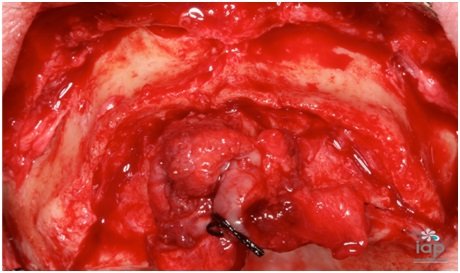

Paciente do sexo masculino, 64 anos de idade, apresentou-se na clinica do IAP- Instituto Sérgio Jayme, no curso de cirurgia avançada.

Sua queixa principal era falta de estabilidade de sua prótese total superior, relatou que perdeu os dentes com menos de trinta anos de idade, ou seja, este paciente usa prótese total a mais de trinta anos.

Após avaliação clinica acompanhada de exames de sangue complementares, foi pedido uma radiografia panorâmica e tomografia computadorizada do maxilar superior. Foi diagnosticada uma grande atrofia da maxila, evidenciando uma reabsorção óssea acentuada em altura e espessura.

Após conversar e analisar as opções de tratamento, optou-se pelo uso do rhBMP-2 (Infuse Bone Graft, 5,6 cc, Medtronic Sofamor Danek USA, Inc), associado ao beta tricálcio fosfato (Bone Ceramic, partículas 500- 1.000 micrometros, Straumann, Basel, Suíça) e telas de titanio (Titanium Augmentation Micro Mesh – 120 x 60mm e parafusos,Ace Surgical Supply Co.,Inc)